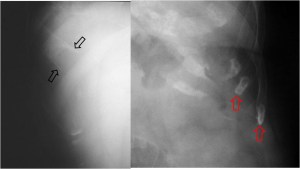

SIGNO DEL TUMOR FANTASMA O TUMOR EVANESCENTE

Signo que describe al derrame pleural atrapado en la cisura menor, especialmente en pacientes con insuficiencia cardiaca. El derrame loculado en la proyección posteroanterior se ve como una lesión nodular o masa que simula un tumor sólido (imagen superior). Sin embargo, la evolución rápida hacia la desaparición de esta lesión sugiere que se trata de derrame.

Vemos en las imágenes un tumor fantasma que desaparece en el control realizado cinco días más tarde.

En la primera imagen, la presencia de derrame pleural asociado y el engrosamiento del resto de la cisura menor, visible como una línea superpuesta al tumor fantasma, sugieren el diagnóstico.